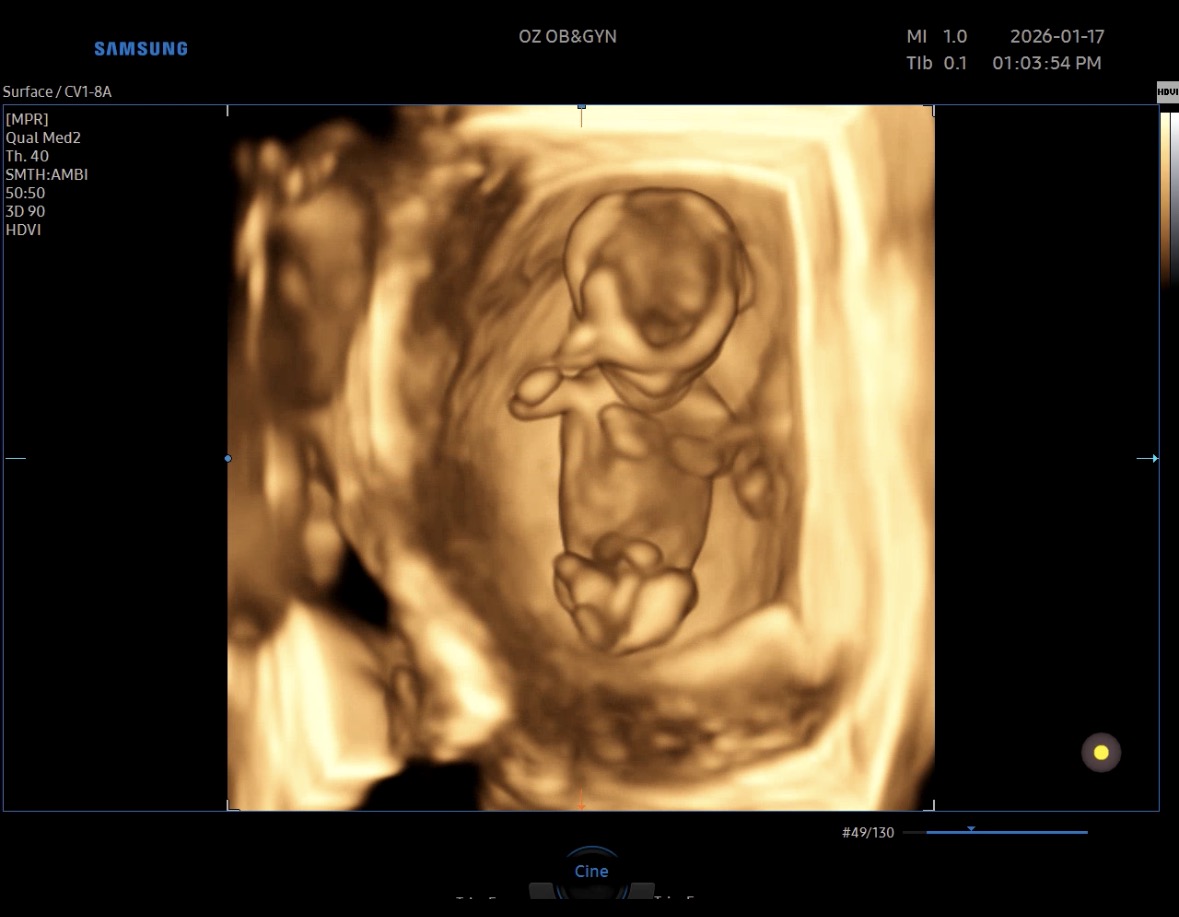

다음날 우리 깜짝이 보러 병원방문

점점 커지는 너의 모습

좀있으면 전신샷은 못찍는다고 하는데

이 귀여운 모습을 못본다니

그래도 엄마 뱃속에서 잘 커줘서 고마워

든든하게 맛있는거 많이 무그께

아빠한테 사달라고 하자 ㅎㅎㅎㅎ

아빠 통장 거덜내기 화이팅!!